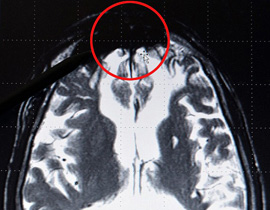

يؤكد البروفيسور وأستاذ طب الأعصاب بجامعة "بريمن" الألمانية، والشهير دولياً بأبحاثه على جينات الدماغ، أنه عثر على ما سماه "بقعة سوداء" في وسطه الأعلى، أطلق عليها اسم "مربض الشيطان" الموسوس للقيام بردات فعل عنيفة ومتنوعة، والكامن كوكر يتربص شراً بالآخرين عند أول إشارة ينشط معها سلبياً، بحيث تنبع منه المحرضات على العنف الفردي والجماعي الفاتك بالآلاف.

بقعة سوداء بالدماغ مسؤولة عن ردات الفعل العنيفة